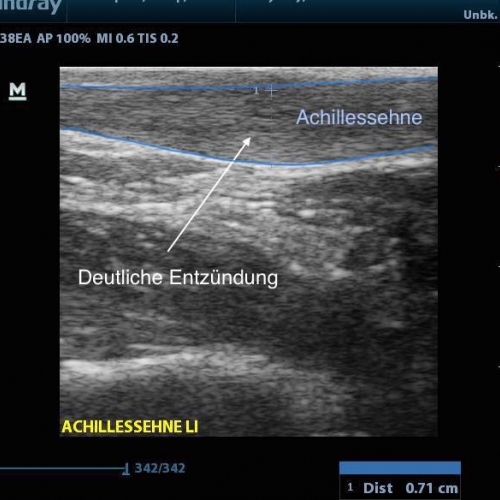

Hierbei werden akustische Wellen (hochfrequente mechanische Schwingungen) durch den Körper geleitet und anschließend von unterschiedlichen Gewebetypen unterschiedlich stark reflektiert. Dies wird dann in ein Bild umgewandelt. Mit entsprechenden Geräten und Wissen lassen sich so viele Diagnosen bestätigen oder ausschließen, angefangen von Muskel- und Bandverletzungen, über Knochenveränderungen bis hin zu Flüssigkeitsansammlungen.

Auch im Rahmen der SPORTMEDIZIN und INJEKTIONSTHERAPIE ist das Sonographiegerät eine tolle Ergänzung. Liegt zum Beispiel ein Muskelfaserriss vor, so kann dieser nicht nur dargestellt und dokumentiert werden, sondern jetzt auch unter Kontrolle ganz gezielt eine Injektion im defekten Bereich gesetzt werden. Auch bei Injektionen an Gelenken wird die Treffsicherheit massiv gesteigert.